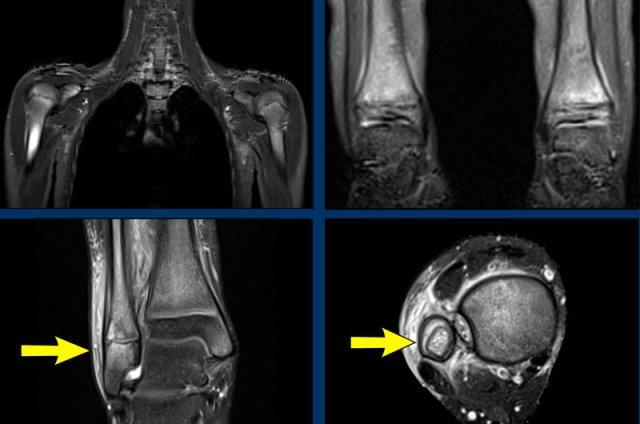

Nhiều ổ CRMO

Bệnh nhân này có các ổ tổn thương ở chỏm xương cánh tay và thân xương cánh tay đoạn gần, mỏm quạ bên phải, và đầu dưới xương chày hai bên.